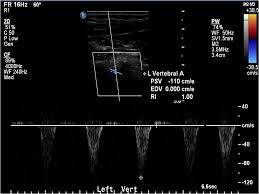

The left vertebral artery spectral wave doppler is seen below the baseline as compared to both left CCA and right vertebral artery. Subclavian steal syndrome occurs secondary to a proximal stenosing lesion or occlusion in the subclavian artery. Features are characteristic of complete left subclavian steal syndrome Features are characteristic of complete left subclavian steal syndrome.

Features are characteristic of complete left subclavian steal syndrome Features are characteristic of complete left subclavian steal syndrome.